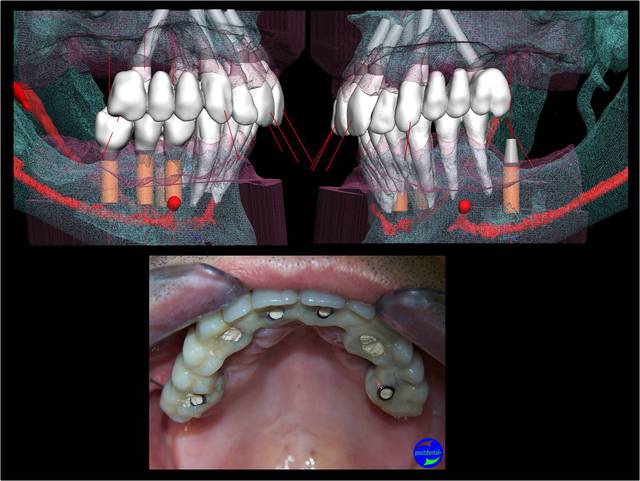

A la mandibule :

Au maxillaire , même moi qui ne suis qu'un petit , petit omnipraticien , et surtout pour le dernier à droite d'implant c'est hallucinant et avec mon expérience en bricolage , bin ce all on5 et demi me fait peur . Je ne vois pas pourquoi virer un bloc antérieur et ne pas profiter des alvéoles de chaque dent , en postérieur attendons que Pp très au fait revienne .

au maxillaire